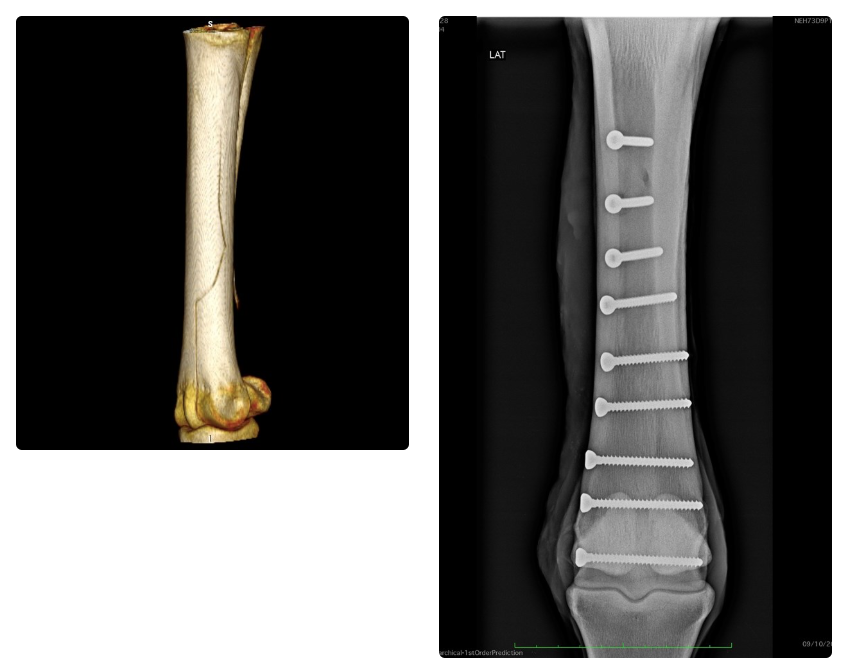

NEH repairs approximately 175 fractures each year. The majority are performed under general anaesthesia, but more simple fractures are repaired standing, under sedation and local anaesthesia. Over the past two decades NEH has refined techniques in fracture repair, with major advances coming from arthroscopic guided repair of fractures involving joints, and CT assisted surgery.

Unique within Europe, NEH runs an in-theatre portable CT unit. Its routine use at NEH has greatly enhanced our understanding of fracture configurations, and contributes to improvements in surgery through CT planning of surgical repair, and CT guided surgery.